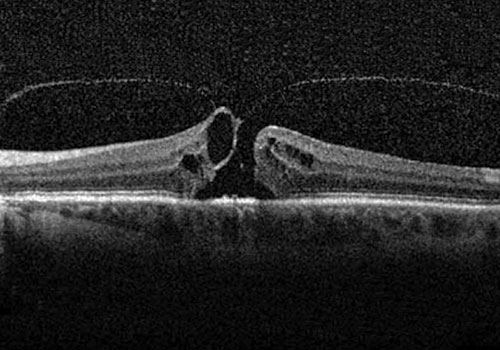

Dettaglio foro maculare

Il foro maculare è una patologia caratterizzata dalla formazione di una soluzione di continuo nella parte centrale della macula ed è associato ad una riduzione della capacità visiva.